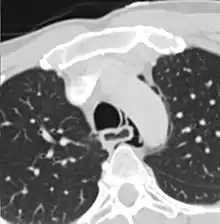

Axial CT image through the upper chest showing extraluminal air (Pneumomediastinum) surrounding the trachea and esophagus | |

The diagnosis of Boerhaave's syndrome is suggested on the plain chest radiography and confirmed by chest CT scan. The initial plain chest radiograph is almost always abnormal in patients with Boerhaave's syndrome and usually reveals mediastinal or free peritoneal air as the initial radiologic manifestation. With cervical esophageal perforations, plain films of the neck show air in the soft tissues of the prevertebral space.

Hours to days later, pleural effusion(s) with or without pneumothorax, widened mediastinum, and subcutaneous emphysema is typically seen. CT scan may show esophageal wall edema and thickening, extraesophageal air, periesophageal fluid with or without gas bubbles, mediastinal widening, and air and fluid in the pleural spaces, retroperitoneum or lesser sac.